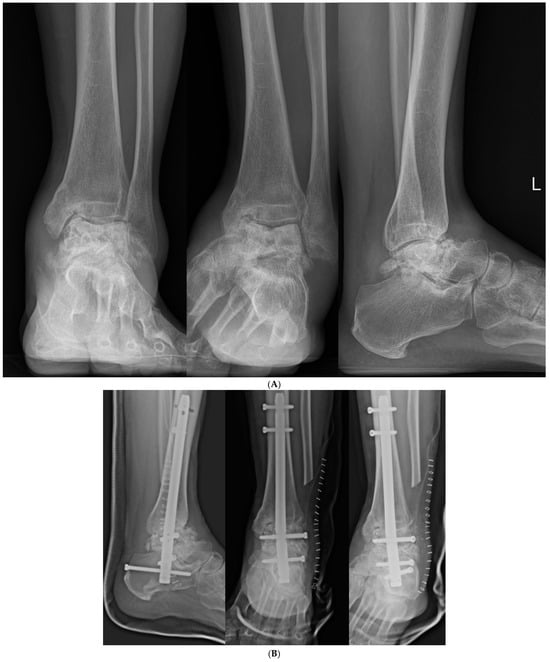

Figure 7. (A) Preoperative and (B) postoperative X-ray Findings.

Jcm 14 02683 g007